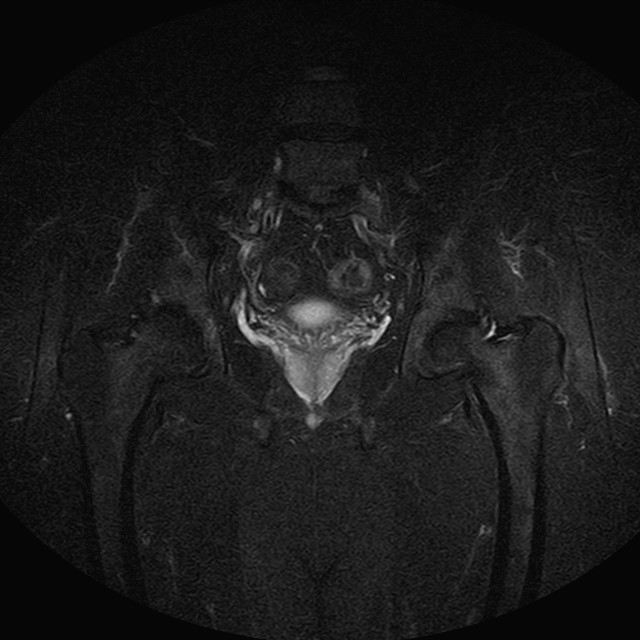

eSTIR

Evidenti e simmetriche alterazioni osteofitosiche in regione coxo femorale con riduzione delle rime articolari. Degenerazione completa del cercine glenoideo. Non attuali segni di versamento articolare. Non segni di edema osseo che escludono attuale algodistrofia od osteonecrosi. Lieve e simmetrica riduzione del trofismo della muscolatura glutea.